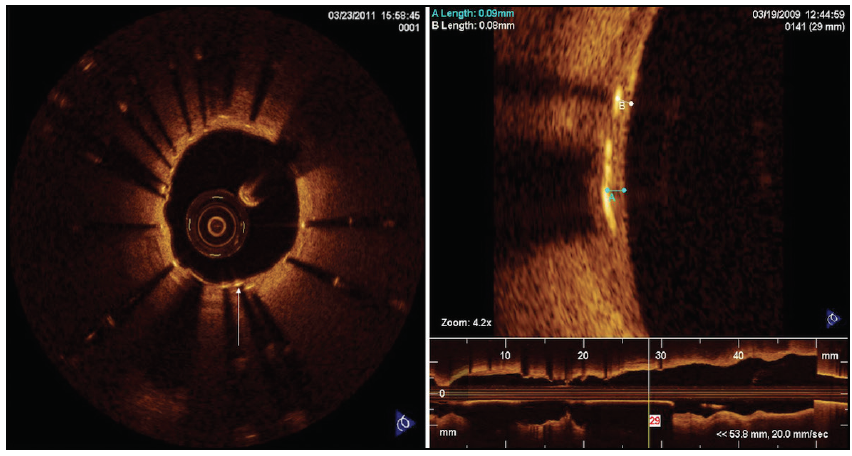

IVUS provides better spatial resolution and is superior to angiography alone in determining lesion severity because it enables precise assessment of vessel wall dimensions and atheroma burden through the assessment of the minimal lumen area (MLA) (Figure 1E).37 A meta-analysis published by Jang et al demonstrated that IVUS-guided DES implantation decreases the rate of major adverse cardiac events, stent thrombosis, and revascularization rates and allows optimal stent deployment.38 In patients with cancer, the use of this adjunctive tool can identify individuals in whom it is safe to defer revascularization based on MLA; this is only helpful for LM lesions, as iFR/FFR should be used for all other lesions. This has been particularly useful when characterizing the functional significance of LM coronary lesions, as evidenced by de la Torre Hernandez et al who demonstrated that it is safe to defer revascularization in the general population with intermediate LM lesions and a MLA > 6 mm2.39

Another important concept is to perform intravascular imaging (IVUS or OCT) to evaluate poststent deployment and ensure that the stent is well apposed and fully expanded, especially when using DESs in patients who may need early discontinuation of DAPT.38,40

OCT has better spacial resolution than IVUS but less power of penetration. It can also demonstrate the presence of thrombus, unrecognized plaque rupture, stent underexpansion, significant edge dissections, and excessive plaque at the stent edges that may be treatable with further stent expansion or the placement of additional stents.41 More recently, OCT has been adopted in the cardio-oncology field when early discontinuation of DAPT is necessary, as it helps to identify patients at lower risk for stent thrombosis (Figure 4).42 In a study published by Iliescu et al, patients who underwent DES implantation between 1 and 3 months prior to the planned procedure and had an indication for noncardiac surgery or biopsy with an increased risk of bleeding were included and followed for 12 months after diagnostic cardiac catheterization with OCT to evaluate the status of the stent.42 OCT images were obtained prior to the planned procedure and stents were considered low risk for thrombosis if the stent struts met the criteria of coverage (> 90% of the total analyzed stent struts), apposition (> 90% of the total analyzed stent struts), expansion, and absence of in-stent restenosis. Among those individuals considered low risk, P2Y12 inhibitors were stopped 5 days prior to the anticipated procedure and restarted 24 hours after with a loading dose. In contrast, those at high risk underwent bridging therapy with low-molecular-weight heparin. In this registry, none of the groups experienced stent thrombosis or cardiovascular death. These findings require further validation by additional studies but are certainly hypothesis generating and might become a useful tool in patients with cancer who require early discontinuation of antiplatelet therapy.

Figure 4. Representative example of the use of OCT images for early discontinuation of DAPT. The patient had a DES placed 1 month previously and required a cancer-related surgical curative procedure that was not possible on DAPT. OCT was performed and the patient was deemed to be low risk for stent thrombosis. DAPT was safely temporarily discontinued with no detrimental outcomes.